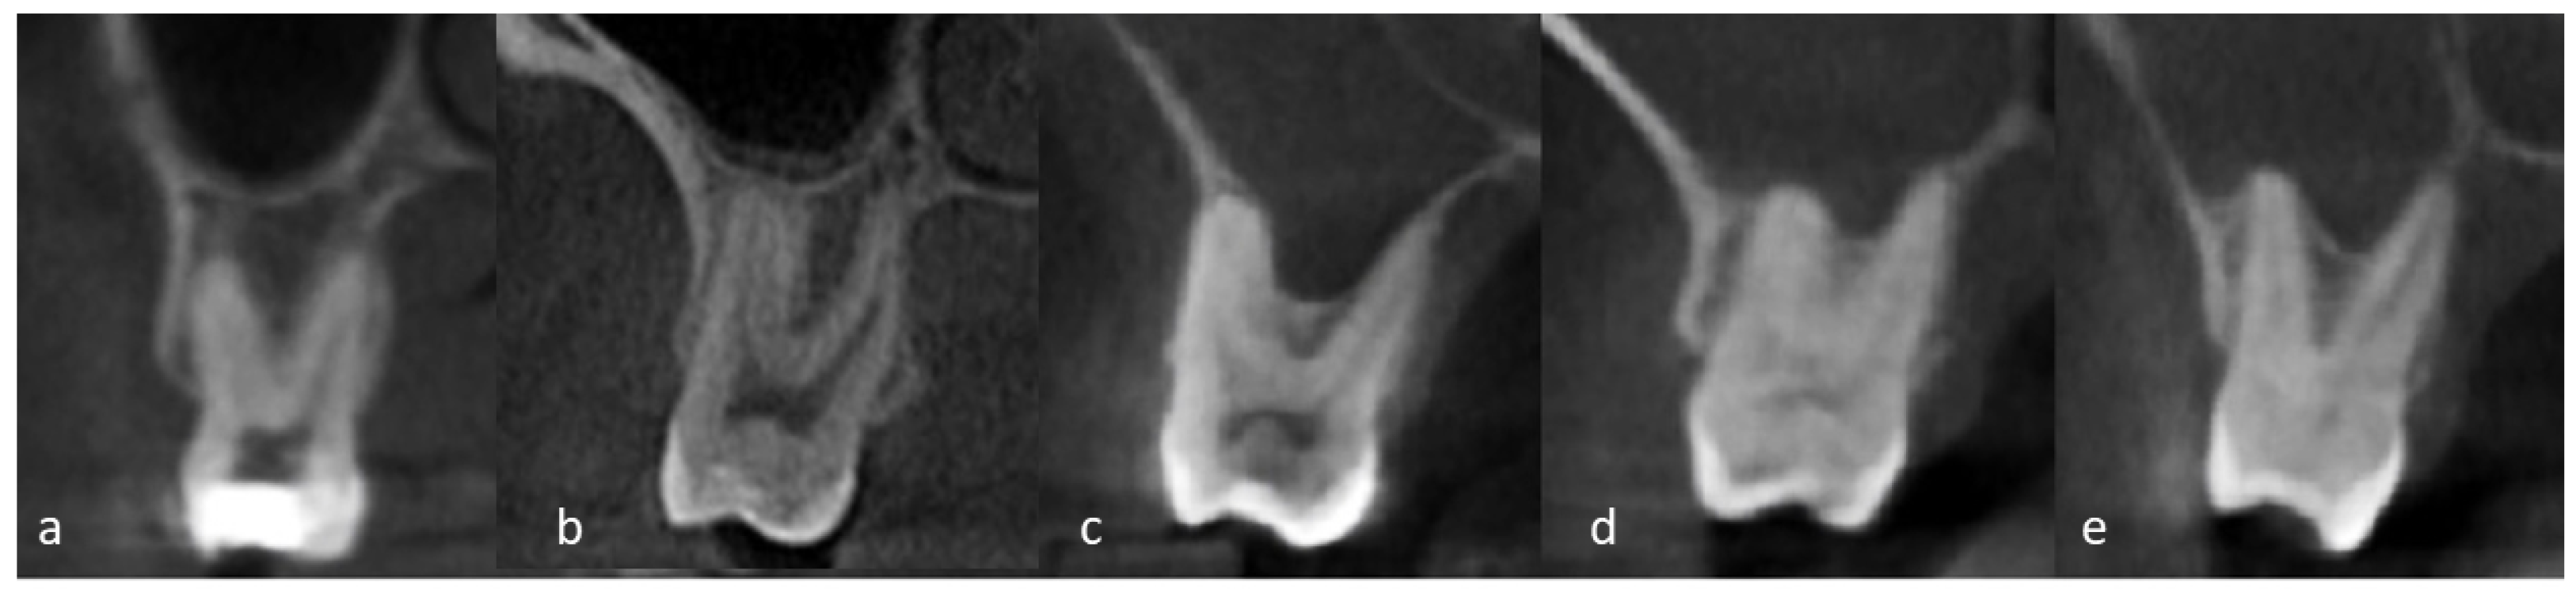

| The relation of roots of posterior maxillary teeth to the sinus floor (RPMT) | Type 0 | 583 | 45.9 |

| Type 1 | 403 | 31.8 | |

| Type 2 | 183 | 14.4 | |

| Type 3 | 77 | 6.1 | |

| Type 4 | 23 | 1.8 | |